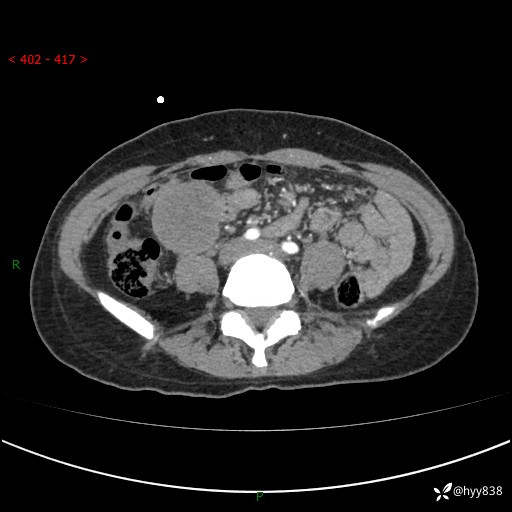

年轻女性,发现腹腔肿物1周。圆圆的肿物,诊断有难度---结果公布~

主诉:发现腹腔肿物1周

现病史:患者自诉于1周前无明显诱因出现剑突下间断性隐痛,尚可忍受,不向其它部位放射,无恶心呕吐、腹泻便秘等不适,于当地市第二人民医院就诊,行CT结果示:1.右中腹占位,间叶组织来源可能2.小肠梗阻3.盆腔积液4.腹腔积液5.副脾6.肝囊肿;于荆州二医行抗炎,抑酸,护胃,补液等对症支持治疗;患者病情好转,今为求进一步诊治,遂来我院门诊就诊,门诊以“腹腔肿瘤”收入院。 起病以来,患者精神、睡眠、饮食一般,大小便正常,近期体力体重无明显改变。

腹部CT增强(外院平扫)